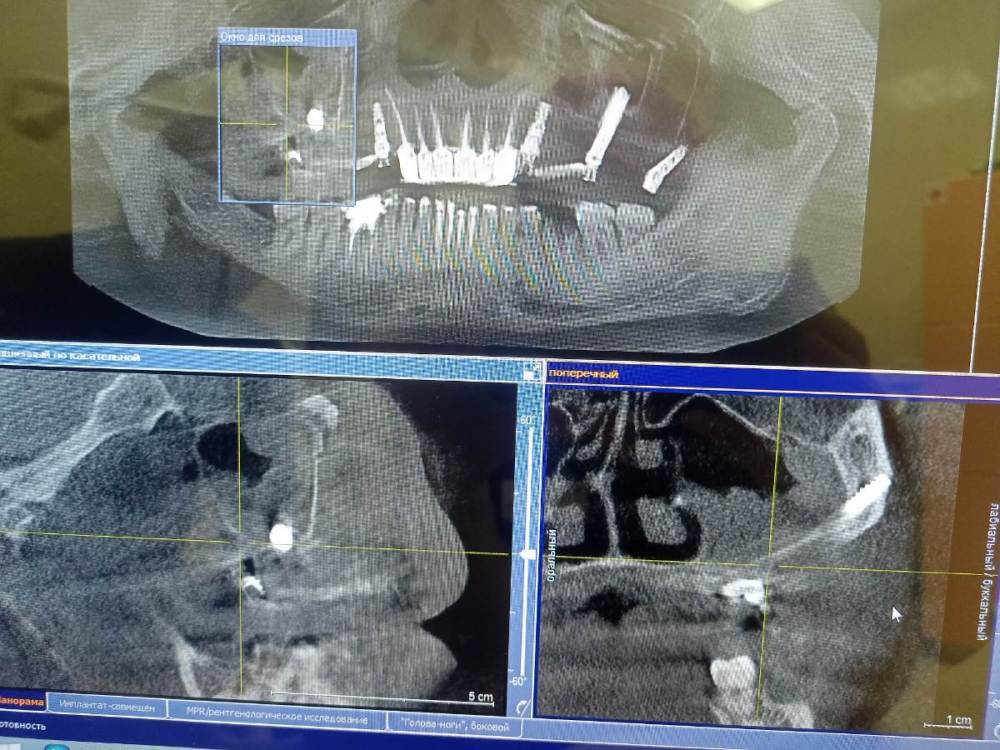

VelikoMu4ennik Опубликовано 30 декабря, 2022 Автор Поделиться Опубликовано 30 декабря, 2022 Все таки съездил в челюстно лицевую больницу. Сделал КТ. Хирург сказал что признаков гноя не виде и выхода импланта к щеке то же. Возможно просто организм не справляется пока с большой травмой. Модные антибиотики назначил и НПВС. Кт прилагаю.... Ссылка на комментарий

Irouil Опубликовано 30 декабря, 2022 Поделиться Опубликовано 30 декабря, 2022 (изменено) Приложите архив с кт, это только фотографии каких-то срезов Но из того, что выложено, поводов считать что с зигомами что-то не так, я не вижу Изменено 30 декабря, 2022 пользователем Irouil Ссылка на комментарий